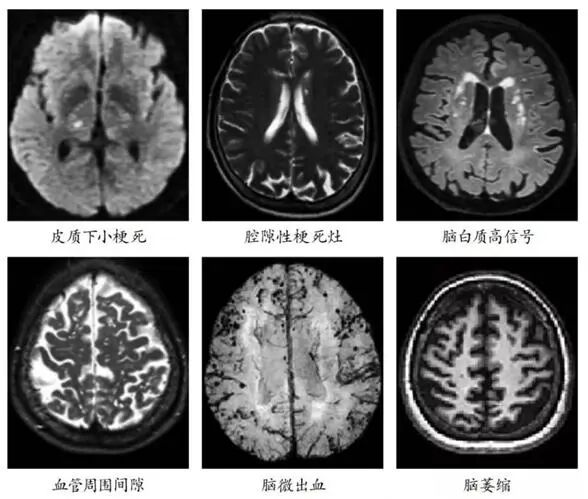

中老年人头颅磁共振(MRI)报告上经常有的腔隙性脑梗死、脑白质高信号等,并非正常衰老的表现,而是脑小血管病(CSVD)的典型信号。CSVD被称作“沉默脑杀手”,因为它早期无症状、进展缓慢,不会引起人们的重视,在不知不觉中损害了患者的运动及认知功能。

脑小血管病,指大脑内直径小于200微米的微小血管(包括小动脉、毛细血管、小静脉)发生退行性病变、堵塞或轻微渗漏,就像脑部深处的“微小水管”慢慢老化、不通畅,进而导致脑组织慢性缺血缺氧,神经功能出现渐进性损伤。

它和我们常说的急性大中风有明显区别:大中风发病急、肢体偏瘫等症状突出,容易被及时察觉;而脑小血管病起病极为隐匿,早期几乎没有特异性症状,进展缓慢,极易被当成正常衰老忽视。临床数据显示,60岁以上人群发病率超30%,90岁以上人群接近100%,也是诱发血管性痴呆、老年人反复跌倒的主要元凶。